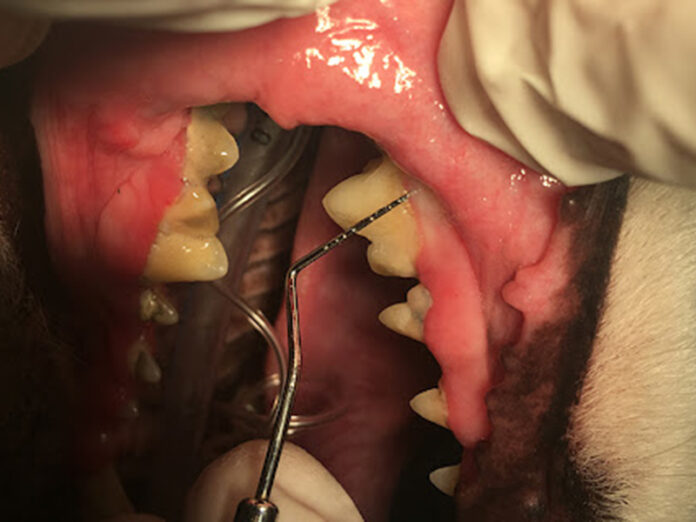

Profesyonel Temizlik Süreci 🏥

Veteriner diş hekimi Dr. Zeynep Hanım anlatıyor:

“Genel anestezi altında ultrasonik temizlik yapıyoruz. İşlem öncesi mutlaka kan testi ve kalp kontrolü yapıyoruz. Acil veteriner durumları için her zaman hazırlıklıyız!”

Diş operasyonu